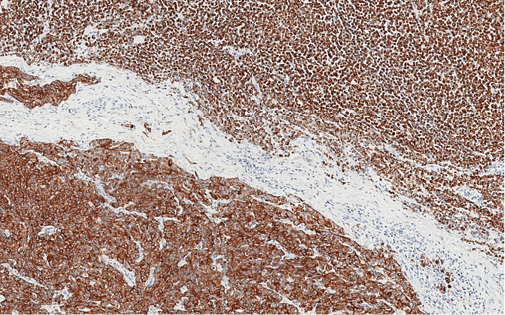

3 pav. Pancitokeratinų ekspresija visame navike ir ryškėjanti diskohezija „rabdoidiniame“ komponente (viršuje, dešinėje pusėje)

Imunohistocheminio profiliavimo metu nustatyta stipri difuzinė PanCK reakcija visuose komponentuose (3 pav.) ir menka, tačiau definityvi MUC2 žarninio tipo mucinų produkcija (4 pav.) kartu su tipiška KRAS geno 12-o kodono mutacija 2-ame egzone leistų klasifikuoti naviką kaip aukšto laipsnio (blogai diferencijuotą) adenokarcinomą. Ieškant biologinio pagrindo neįprastai naviko morfologijai paaiškinti atliktos papildomos imunohistocheminės reakcijos: Hep-Par1 (neigiama), INI1 (praradimo nėra), BRAF (neigiamas, tikėtina, nemutuotas), PMS2 ir MSH6 (reakcija išlikusi, nėra mikrosatelitų nestabilumo audinyje požymių), visose naviko ląstelių populiacijose patvirtintas jau biopsijoje identifikuotas difuzinis neuroendokrininis fenotipas (100 % Synaptophysin ir 95 % Chromogranin A ekspresija (5 pav.)). Ki67 proliferacinis aktyvumas buvo heterogeniškas ir rabdoidinės išvaizdos komponente siekė 90 proc., o likusiuose buvo perpus žemesnis (6 pav.).